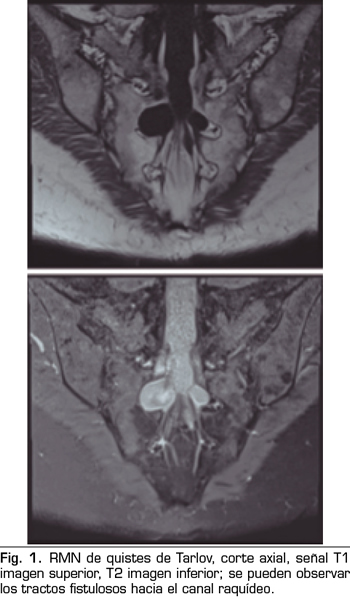

Se realiza una RMN donde no se observan alteraciones estructurales que justifiquen las dolencias que presenta. Como hallazgo casual se describen quistes de Tarlov a nivel de S2. Se solicita una valoración por el servicio de neurocirugía, quienes dudan que la clínica sea consecuencia de los quistes (Figuras 1 y 2).

Una de las causas de dolor crónico a tener en cuenta son los “quistes perineurales” o “quistes de Tarlov”. Desde su primera descripción en 1938, son numerosos los artículos en los que se hace referencia. Se trata de lesiones nerviosas que se producen más frecuentemente en la zona sacra (8). En un estudio de Paulsen RD sobre la prevalencia y el drenaje de los quistes de Tarlov, se observó que en 500 pacientes que se sometían a una Resonancia Magnética (RMN) por dolor lumbar, el 5 % presentaba quistes de Tarlov y un 20 % de esos pacientes padecían síntomas relacionados con ellos (9,10). El diagnóstico suele ser casual mediante RMN; la cifra es variable debido a que solo se solicita a aquellos pacientes que presentan dolor lumbar crónico. Dicha técnica es más sensible que la tomografía axial computerizada (11,12).

Los “quistes perineurales” o “Quistes de Tarlov” son alteraciones en la duramadre de las raíces nerviosas, que se producen más frecuentemente en la zona sacra. El diagnóstico suele ser casual mediante RMN; la incidencia es variable, debido a que el hallazgo es incidental. Habitualmente son asintomáticos, pero pueden producir radiculopatía, dolor perineal o vejiga neurógena, entre otros.

No obstante, debemos tener en cuenta las variaciones anatómicas como son los quistes de Tarlov, a expensas de las capas más internas de las meninges, la piamadre y el aracnoides. Estos quistes principalmente se sitúan en la zona sacra y lumbar, y suelen diagnosticarse de manera incidental en el transcurso de una RMN. Aunque la clínica producida por los mismos no es frecuente, se deben tener en cuenta como posible diagnóstico diferencial ante posible dolor lumbar crónico.